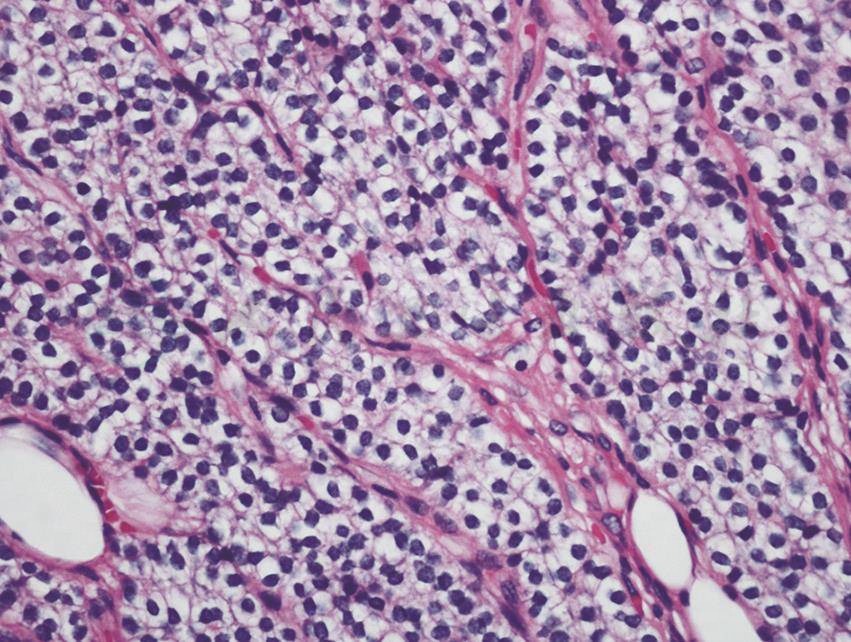

镜下见双肺各叶段支气管通畅,未见气管、支气管内明显异常。支气管肺泡灌洗液抗酸杆菌涂片阴性。经支气管肺活检(TBLB)见右肺下叶肺泡腔及肺泡隔多量钙化物沉积(图4)。

图4 经支气管肺活检病理结果(HE染色,200×)

引自:主编:.呼吸系统疑难病例诊疗辨析.第1版.ISBN:978-7-117-26415-0

根据辅助检查结果,考虑本病例病因为原发性甲状旁腺功能亢进,手术切除甲状旁腺,病理检查显示为甲状旁腺腺瘤。甲状旁腺激素分泌过多可致高钙、低磷。本例患者钙磷乘积在正常范围内,经支气管肺活检见肺泡腔及肺泡隔有多量钙化物沉积,胸部CT见两肺散在斑片状影,99mTc-MDP骨闪烁显像见双侧肺野骨外显影,排除了肺结核、矽肺等常见疾病。因此,本病例诊断为甲状旁腺腺瘤伴发转移性肺钙化。